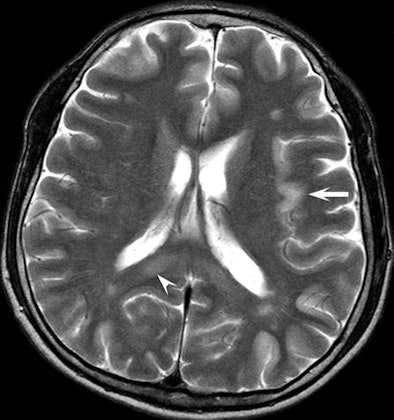

Above is a T2-weighted MR image of bilateral patchy hyperintense lesions in the cerebral cortex, including the insula (arrow). There is also involvement of the splenium of the corpus callosum (arrowhead). On the corresponding diffusion-weighted MR image below, the hyperintense lesions are more prominent than above. |